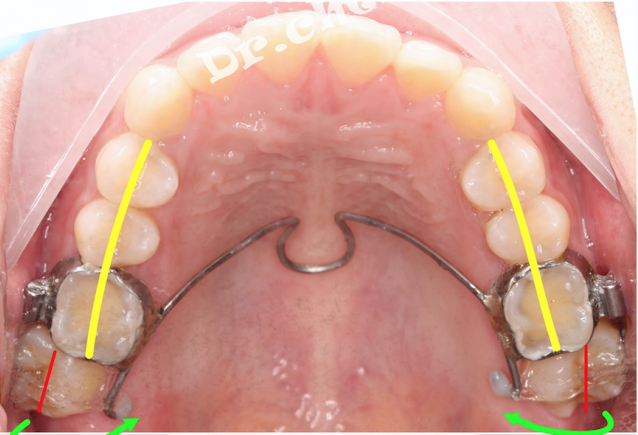

可以看出向下的力过猛,牙根露出来了,所以向下的力要足够的小,初期矫治以向内的力为主。(理想情况是切线力)

这个方案也暴露出隐形矫治的一个风险(隐形牙套似乎没法佩戴口外弓)